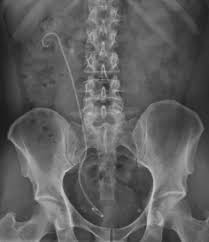

Sonda Cook, sau sondă dublu J (JJ), este un dispozitiv medical folosit în urologie pentru a menține deschiderea ureterului și a permite drenajul eficient al urinei din rinichi către vezica urinară. Aceasta este flexibilă, are o formă curbată la ambele capete, asemănătoare literei „J”, și este fabricată din materiale biocompatibile, precum siliconul sau poliuretanul, pentru a asigura confortul și siguranța pacientului. Sonda este utilizată în diverse situații, inclusiv obstrucții urinare sau după intervenții chirurgicale.

Sonda Cook este concepută să mențină deschis ureterul, tubul care transportă urina de la rinichi la vezica urinară, prevenind obstrucțiile și asigurând drenajul constant al urinei. Cele două capete curbate în formă de „J” se fixează unul în rinichi (calicele renale) și celălalt în vezica urinară, pentru a preveni migrarea sau deplasarea sondei.

- Ghidajul sondei: Un ghidaj subțire (sârmă flexibilă) este introdus prin ureter până la rinichi, folosind imagistica radiologică sau ultrasunete pentru a verifica poziția. Sonda Cook este apoi glisată peste acest ghidaj, fiind plasată cu capătul superior în rinichi și capătul inferior în vezica urinară.

- Fixarea sondei: Cele două bucle în formă de „J” se formează automat la ambele capete pentru a fixa sonda în poziție și a preveni deplasarea.

- Verificare finală: Poziția sondei este confirmată prin imagistică pentru a asigura o plasare corectă.